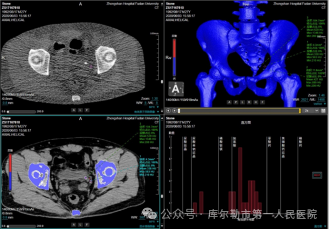

1、无限制心血管成像-单心动周期成像

超高端320排的宽体探测器单圈扫描即可覆盖全心,搭配业内最快转速和独家AI冠脉追焦技术,不管是对于心律不齐,还是高心率等一般CT做不了的心脏检查的情况,超高端320排都能在单心动周期内获得优质图像。真正做到“心跳随意、扫描不止”。同时配合快速扫描和切换扫描方式等技术还可以实现大范围血管联合扫描成像。

5、功能成像方案

能谱成像技术:分析人体病灶的组织成分、组织特性,为影像诊断提供常规CT无法提供的重要信息,如进行痛风石检测、泌尿系结石成分分析、碘与钙质区分、肿瘤同源性鉴别等。

▲ 痛风石检测

▲ 泌尿系结石分析医院仪器怎么成像【医院动态】库尔勒市第一人民医院医学影像科引进新设备,助推医院高质量发展_https://www.jmylbn.com_新闻资讯_第21张